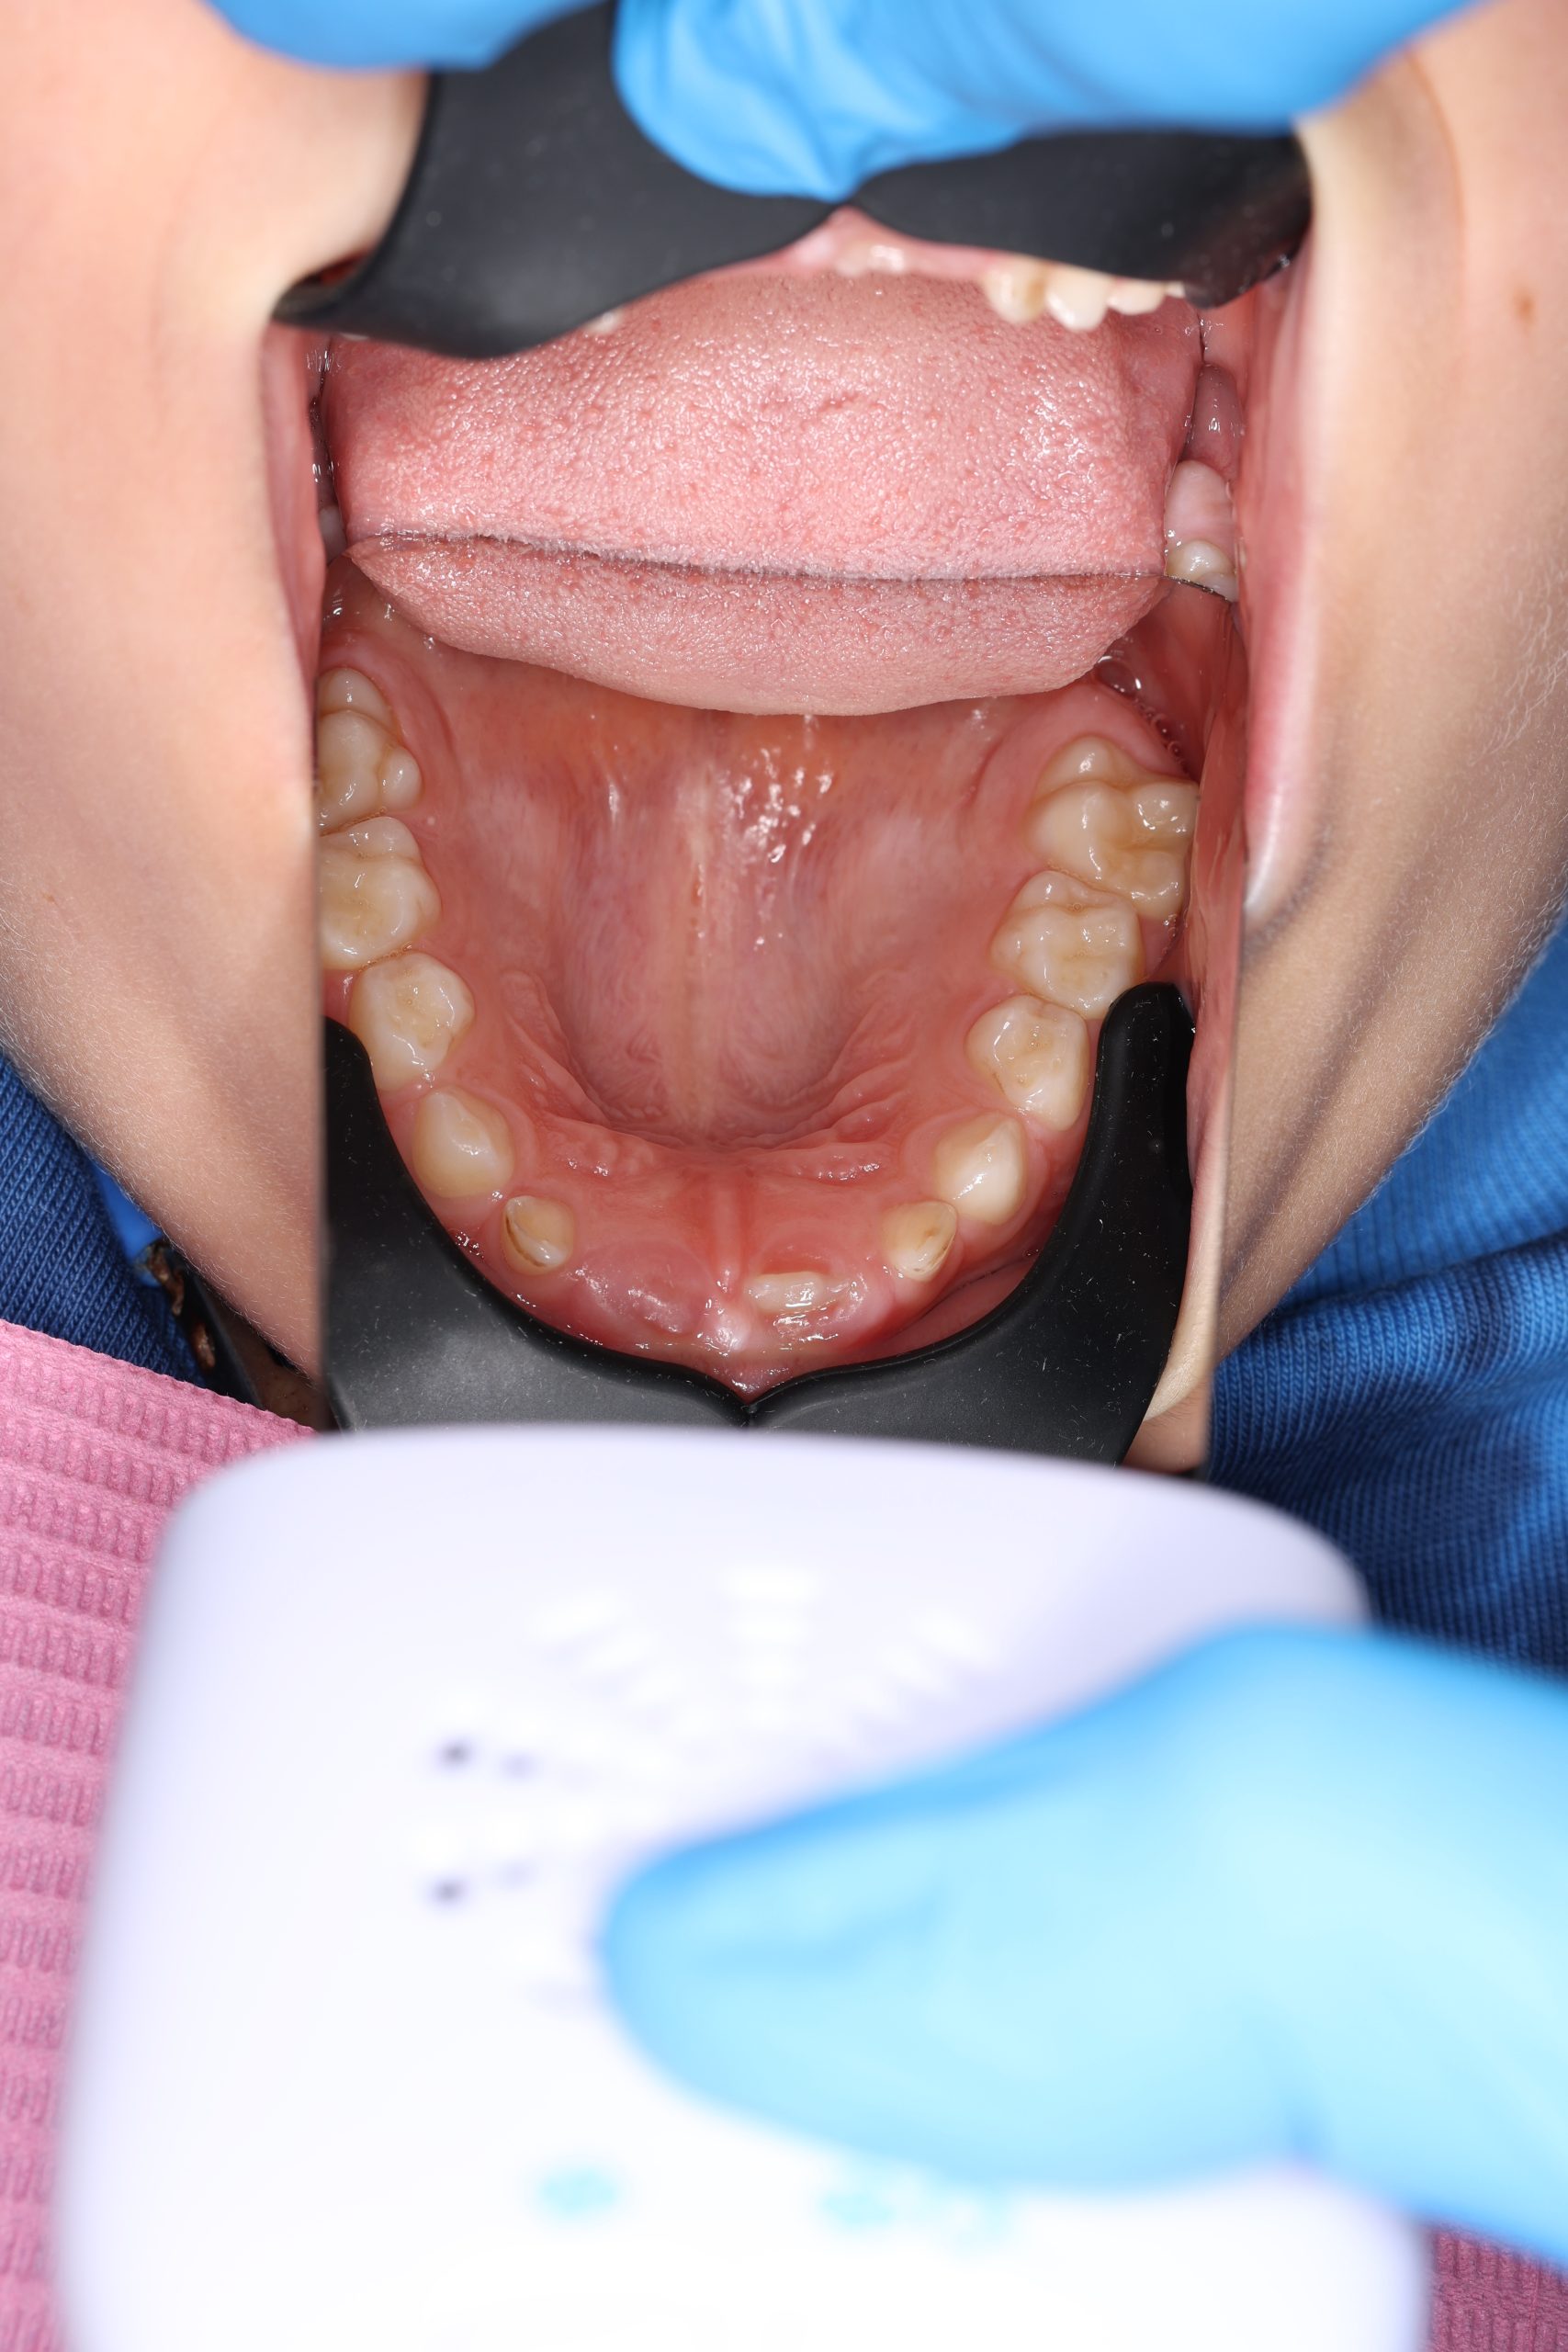

We examine the condition of teeth, gums, and bite. - Plaque Disclosure with Special Indicators

Areas that weren’t cleaned well appear purple. The darker the shade, the older the plaque. This helps both kids and parents understand where brushing needs to improve. - Brushing Training & Home Care Tools Selection